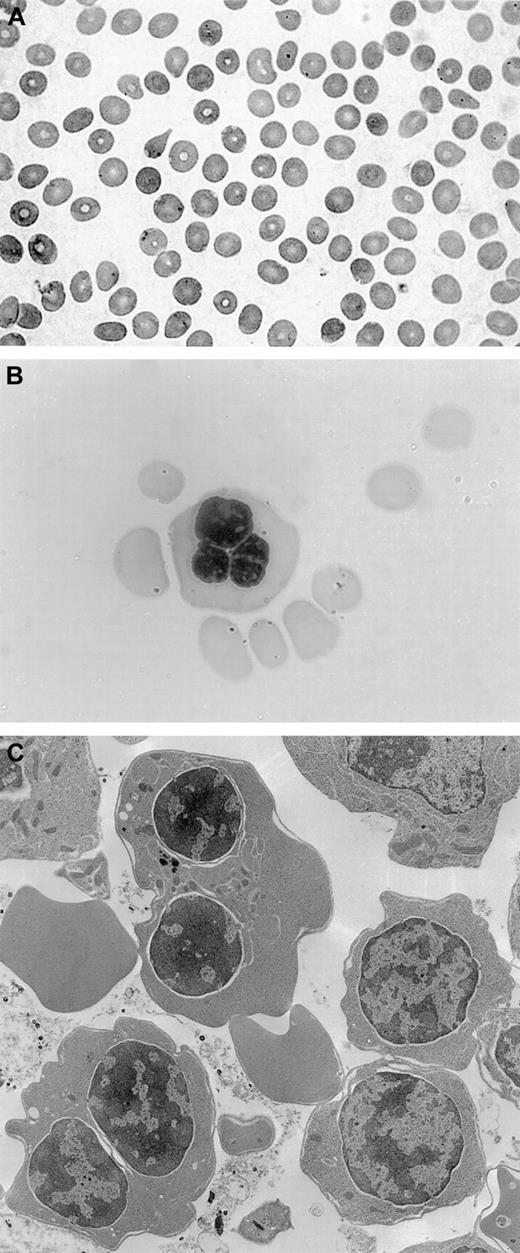

The patient underwent a bone marrow aspirate and biopsy, which showed normal myelopoiesis, dyserythropoiesis, and more than 20% binucleated erythroblasts. No karyotypic alterations were detected. Electron microscopy analysis revealed double membranes on the majority of erythroid precursors; the negativity of the Ham test oriented to a diagnosis of CDA type II with variant features.14Peripheral blood smear, bone marrow aspirate, and electron microscopy findings are shown in Figure 1.

Fig. 1.

Peripheral blood smear, bone marrow aspirate, and electron microscopy findings.

(A) Peripheral blood smear, showing macrocytosis. (B) Bone marrow aspirate with a multinucleated erythroblast. (C) Electron microscopy findings with evidence of double membranes on erythroid precursors.